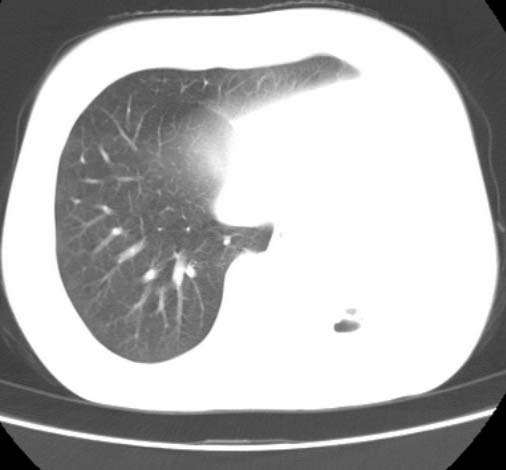

女  20岁。一月前咳血,诊“肺结核”抗痨治疗一月后,咳血停止,现复查。病人精神好。前后ct片对比未见明显变化。既往体检“正常”

1)考虑左肺结核并肺不张、支气管扩张。2)纵隔疝。

以前体检正常只能考虑左肺结核并肺不张、支气管扩张。2)纵隔疝。

考虑左肺结核,左肺毁损,纵膈左偏,既往体检正常不可靠,tb一个月也不会这个样子的,有钙化,应该病程较长,冰冻三尺非一日之寒!

左肺发育不全。

考虑左肺结核,左肺毁损,纵膈左偏,既往体检正常不可靠,tb一个月也不会这个样子的,有钙化,应该病程较长,冰冻三尺非一日之寒

结核,左肺毁损。